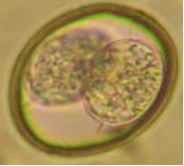

Cystoisospora spp. (Cystoisosporiasis);

Oocysts (shed in feces);

~20-53 X 10-43 µm - Broadly oval, colorless to pinkish, no micropyle or micropylar cap.

Sporulated containing 1x2x4 architecture (2x sporocysts X 4x sporozoites = eight total).